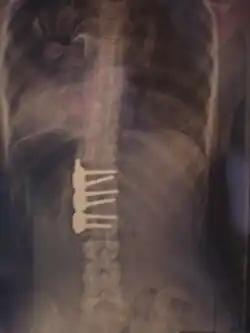

Хирургическое лечение

При неуспехе бескровного консервативного лечения из-за нарушения предписанного режима ношения корсета, плохого качества изготовленного корсета или отказе от него рассматривается операция по установке металлических конструкций и аутотрансплантантов (небольших фрагментов кости таза пациента, превращённых в костную крошку) фиксирующих между собой тела позвонков, называемая «спондилодез» или «fusion»-закрепление(слияние, заваривание).

При оперативном лечении искривлённая часть позвоночника выпрямляется до определённого возможного угла при помощи металлических стержней и шурупов (т. н. транспедикулярных винтов), что ведёт к полному обездвиживанию этих отделов позвоночника. Операция при сколиозе подходит прежде всего для сильных искривлений, которые больше не могут лечиться другими методами. Оперативная фиксация может предотвратить дальнейшую прогрессию и ухудшение состояния.